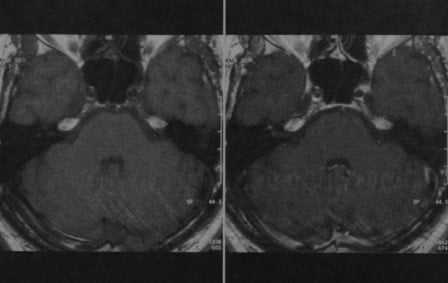

Усиление по ходу лицевого нерва после введения гадолиния у мальчика 15 лет с остро возникшим невритом правого лицевого нерва.

CISS-последовательность: незначительный отек канала лицевого нерва. Фронтальная проекция: выраженное усиление лицевого нерва в его канале.